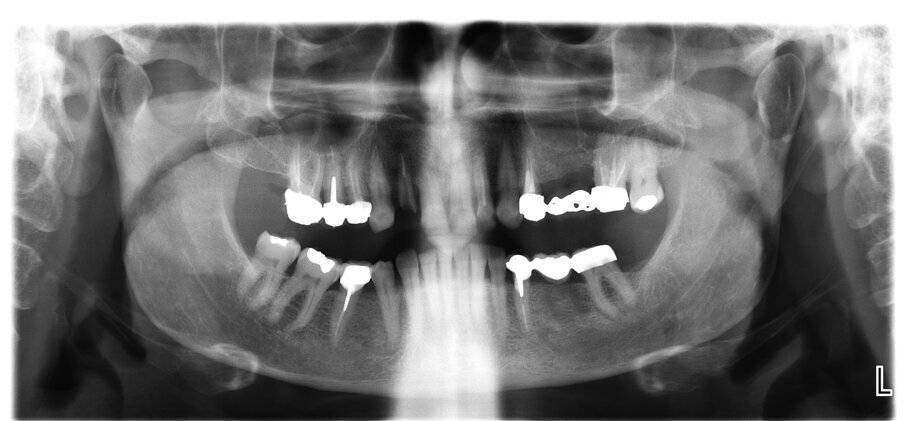

Un paziente di 66 anni, con anamnesi patologica di NIDDM ben compensato e cardio-vasculopatia ischemica in buon compenso farmacologico, si presenta alla nostra attenzione per ascesso parodontale alla radice residua del dente 1.2 e per multiple fratture dei manufatti protesici esistenti (Figg. 1-6). È evidente la presenza di grave malocclusione con perdita di VDO, usure e fratture dei restauri protesici e dei denti residui, presenza di abfractions cervicali. Il paziente evidenzia alla visita modesta dolenzia muscolare alla palpazione, specie a carico dei muscoli pterigoidei mediali e temporali, apertura della bocca ridotta e lieve rumorosità delle TMJ.

L’infezione a carico della radice del dente 1.2 è immediatamente attribuibile a frattura verticale con sondaggio positivo di 9 mm (Fig. 7). Estratta la radice di 1.2 fratturata, il paziente richiede una riabilitazione protesica fissa all’arcata superiore che preveda il minor numero possibile di interventi endodontici e chirurgici. Viene da noi proposta una riabilitazione protesica full arch che consenta, previo studio del caso gnatologico e terapia interlocutoria con provvisori in PMMA, la definizione di un’occlusione a funzione sequenziale in TRP per l’aumento controllato della VDO e la stabilizzazione dei rapporti articolari, ora visibilmente compromessi.

Si esegue perciò cefalometria (Fig. 8) su radiografia latero-laterale (Fig. 9) e axiografia dei movimenti limite (Cadiax Compact, Gamma Dental) (Fig. 10) per la programmazione di un articolatore a valori medi (Artex TR, AmmanGirrbach) e montaggio dei modelli con arco faciale, che confortano nella produzione di un primo provvisorio prelimatura con rialzo arbitrario della VDO di 5 mm sull’asta incisale e miglioramento di OB e OJ, a scopo pre-terapeutico interlocutorio e di immediata risoluzione estetica. Conclusa la necessaria terapia causale e restaurativa viene eseguita la scansione intraorale delle arcate (TRIOS 3 Pod, 3Shape) (Figg. 11-14) e del rapporto articolare con cera di RP (Fig. 15). La scansione è stampata (VisiJet RWT, 3D Systems) con monconi sfilabili tramite stampante 3D (ProJet MJP 2500 Plus, Selltek) (Figg. 16-20), i modelli derivanti sono zoccolati e montati con cere di RP e arco faciale su articolatore a valori individuali (Reference SL, Gamma Dental). La programmazione dell’articolatore derivante dalla registrazione axiografica è ora eseguita come da indicazioni del software (Gamma Dental software, sia per l’uso degli inserti condilari ed incisali, sia per la definizione degli angoli di SCI e di Bennet (Fig. 21). Lo spazio protesico risultante a una VDO adeguata alla riabilitazione dei denti anteriori vitali, con anatomia non ulteriormente modificabile, è insufficiente per uno stabile ripristino dei rapporti occlusali, specie nei tragitti funzionali. Si decide perciò di impiegare due inserti rossi di programmazione di protrusiva (+2 mm) per riposizionare la mandibola in TRP (Figg. 22, 23).